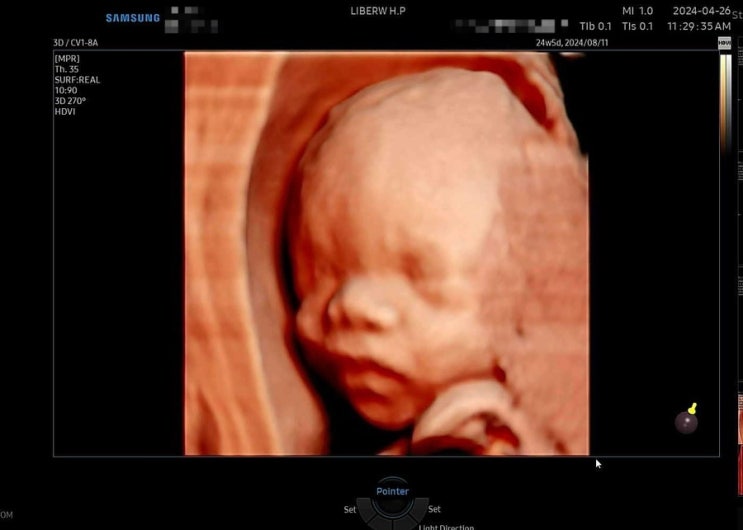

[임신 24주] 중기 입체초음파

임신 24주차! 시간이 정말 빠르다. 24주 5일차에 정기검진을 다녀왔다. 임신 중기에는 4주에 한번씩 정기검...